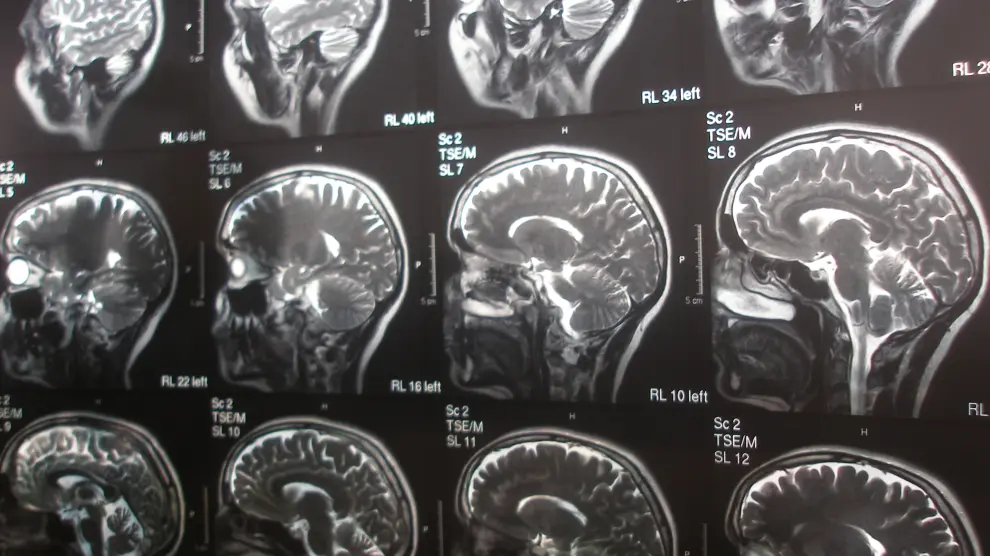

Tu cerebro es plastilina

Varios estudios han demostrado que el cerebro no tiene por qué atrofiarse con la edad.

La frase: "Soy así, no puedo cambiar" debería quedar desterrada para siempre de nuestro vocabulario. Sobre todo después de que los expertos en la mollera humana haya demostrado por activa y por pasiva que la plasticidad neuronal se mantiene durante toda la vida, y "la evolución personal depende de qué hagamos con el cerebro, qué le pidamos, con qué le alimentemos en todos los sentidos". Así lo cuenta en su blog de neurociencia José Ramón Alonso, Director del Laboratorio de Plasticidad neuronal y Neurorreparación del Instituto de Neurociencias de Castilla y León.

Después de todo a estas alturas no cabe duda de que, con la edad, el cerebro no tiene por qué perder neuronas ni atrofiarse. Lo que aún queda por aclarar es qué factores contribuyen a que el cerebro sea moldeable a edades avanzadas. Uno de los más evidentes, de momento, es el ejercicio físico. Pequeñas caminatas, rápidas y regulares, detienen la pérdida de volumen cerebral y mantienen a raya el deterioro de las habilidades mentales asociadas a la edad. Alonso destaca una investigación de la Universidad de Pittsburgh que demostró que con este tipo de actividad, la corteza prefrontal y el hipocampo incrementaron su volumen entre un 2 y un 3%, una cantidad modesta pero importante en un período de la vida en que lo normal es la atrofia paulatina.